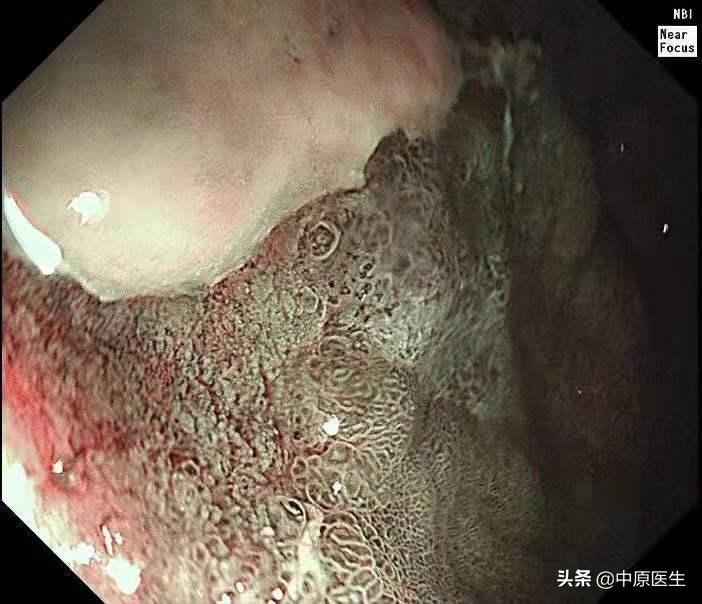

这个患者的溃疡多发,不算太大,并且表面的苔很干净,底部也算平坦,尤其是新发现的两个溃疡,从这几个条件来看,似乎良性可能性大。但是,我还是不放心。我现在只是用了白光检查,为什么不选择窄带光,放大检查?虽然麻烦一点,但是,可以看到更多细节!于是,我打开NBI模式,并且使用变焦(俗称放大,可以达到和显微镜下看类似的效果),再仔细地对每一处病变进行了观察,结果竟然发现,虽然范围很小,尤其是胃窦处的溃疡,不超过2个毫米的范围内我都发现了腺管缺失和血管异常扩张的地方,这往往提示病变有可能已经癌变,在放大镜的引导下,我对病变进行了精准活检。